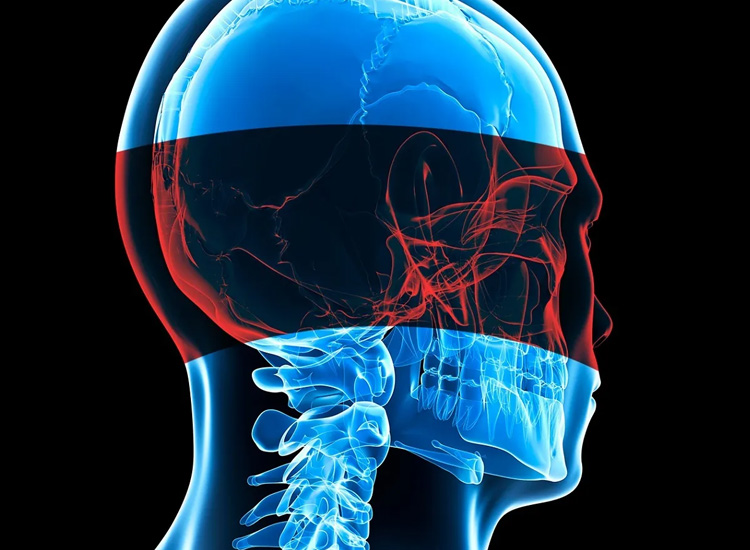

It gives us great pleasure to invite you to the forthcoming edition of SKULLBASECON 2026, which

will be held in Hyderabad, India with the theme - Unified Skull Base. This prestigious

conference continues to serve as a significant academic platform dedicated to advancing the

field of skull base surgery and neurosurgical sciences.